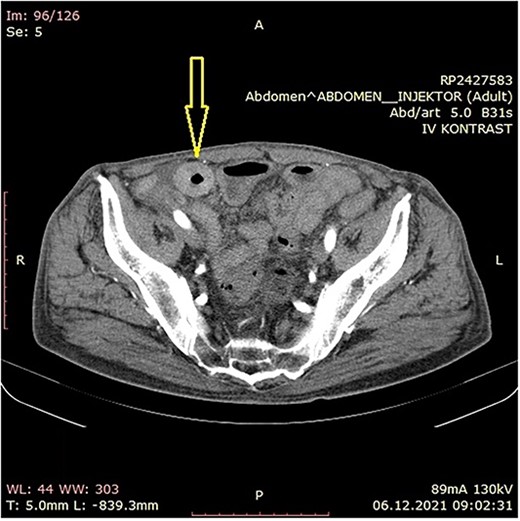

The patient was initially treated with monthly intramuscular doses of 20 mg of octreotide LAR (long-acting somatostatin analog) over a period of 5 months. During this period, the patient subsequently developed gradual partial small bowel obstruction, manifested with episodes of cramp abdominal pain and difficulties in bowel movement. Abdominal computerized tomography (CT) scan and MR imaging enterography were indicated. CT scan confirmed the presence of liver metastases and thickened small bowel wall with no confirmation of primary tumor existence (Fig. 1). MR enterography revealed small bowel distension with visible zone of transition in the right hemi abdomen (ileum) with restriction of diffusion (low signaling of apparent diffusion coefficient map) with surrounding desmoplastic reaction and visible irregular tumor with measured dimensions of 24 × 18 mm (Fig. 2).

Abdominal CT scan showing small bowel wall thickening described as chronic small bowel obstruction (arrow).